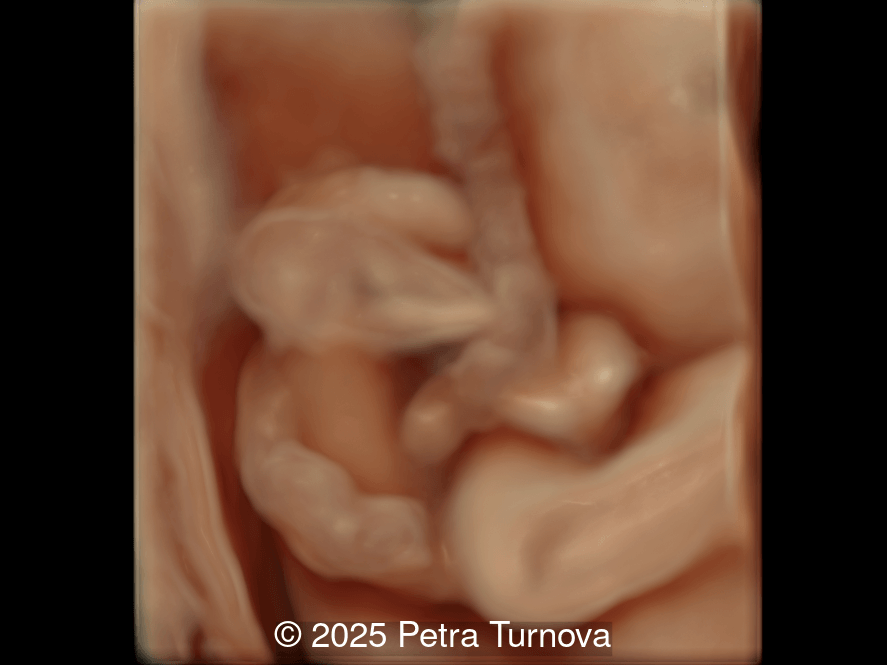

A woman with no significant medical history presented to our center at 20 weeks and 5 days for fetal anatomic survey. The following findings were observed:

Image 3

Our imaging revealed malformations in all four limbs with elbow, wrist, and knee joints fixed in extension, as well as foot and ankle malformations. Profile abnormalities were observed with prefrontal edema, flat profile and retro-micrognathia. Ultrasound demonstrated minimal stomach filling related to a lack of swallowing ability and hypoplastic lungs due to poor diaphragmatic movement. Nuchal edema was present.